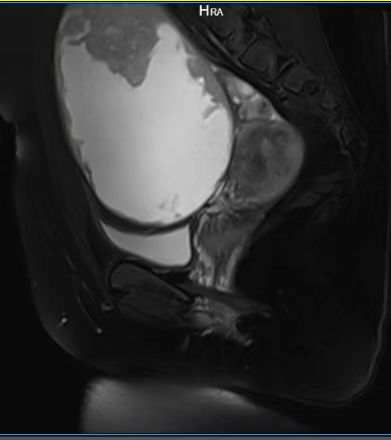

近日,我院妇科团队成功为一名13岁少女实施单孔腹腔镜下盆腔巨大卵巢囊肿剥离术,标志着我院妇科微创技术迈入新阶段。

患者因发现盆腔包块就诊,经检查诊断为直径达15cm的卵巢囊肿。考虑到患者年龄小、未婚且对术后美观要求高,妇科团队决定采用经脐单孔腹腔镜技术,仅通过脐部一个1-2cm的小切口完成手术。术后患者恢复迅速,腹部几乎无可见疤痕,目前已顺利出院。